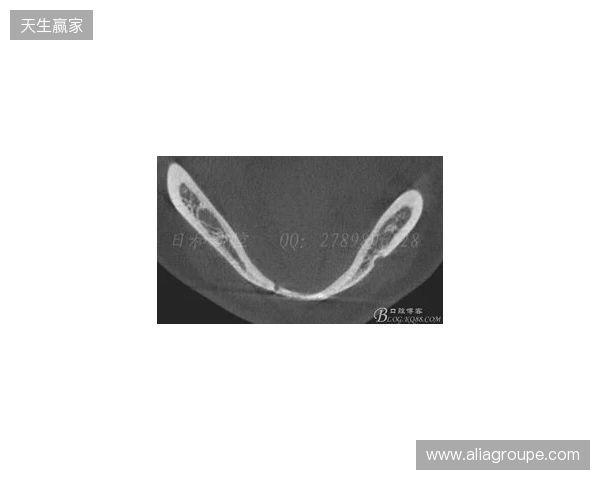

在2026赛季中超联赛首轮的比赛中,韦林顿·席尔瓦遭遇了严重的伤病,导致他上唇部受伤,并且出现了牙齿和牙槽骨的损伤。根据华西口腔医院的诊断,席尔瓦的伤情包括上唇部贯通伤、两颗牙齿半脱位以及上颌前牙区牙槽骨骨折。此事件不仅对球员本人构成了巨大的身体挑战,也给球队带来了不小的影响。伤病的发生让人揪心,球迷们纷纷为席尔瓦送上祝福,希望他能尽快康复,重返赛场。

根据医院的检查结果,韦林顿·席尔瓦的上唇部受伤程度较为严重,属于贯通伤,已经进行了清创缝合。这种类型的伤势不仅影响外观,还可能对球员的饮食和发声造成影响。更为严重的是,他的上颌前牙区还出现了骨折,意味着席尔瓦在恢复期间将面临长时间的治疗和康复过程。

球员的第11和第21牙出现了半脱位的情况,这可能会导致他在恢复后需要进行进一步的牙科治疗,甚至有可能影响到他今后的职业生涯。医生表示,虽然通过手术和治疗可以恢复,但心理层面的恢复同样重要。